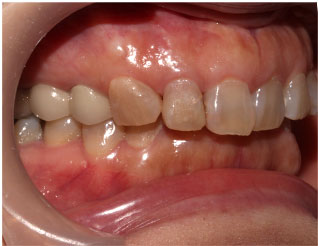

- ブリッジ 症例写真 B-0110オールセラミッククラウン4本 男性モニターの方です。

この方はご来院時には前歯や奥歯に欠損部分がありました。 当院では1回目の治療時に仮歯を入れますので、すぐに見た目が気にならなくなります。 上下の歯の治療を同時進行で治療しますので、通院回数は保険診療よりも少なく済みます。